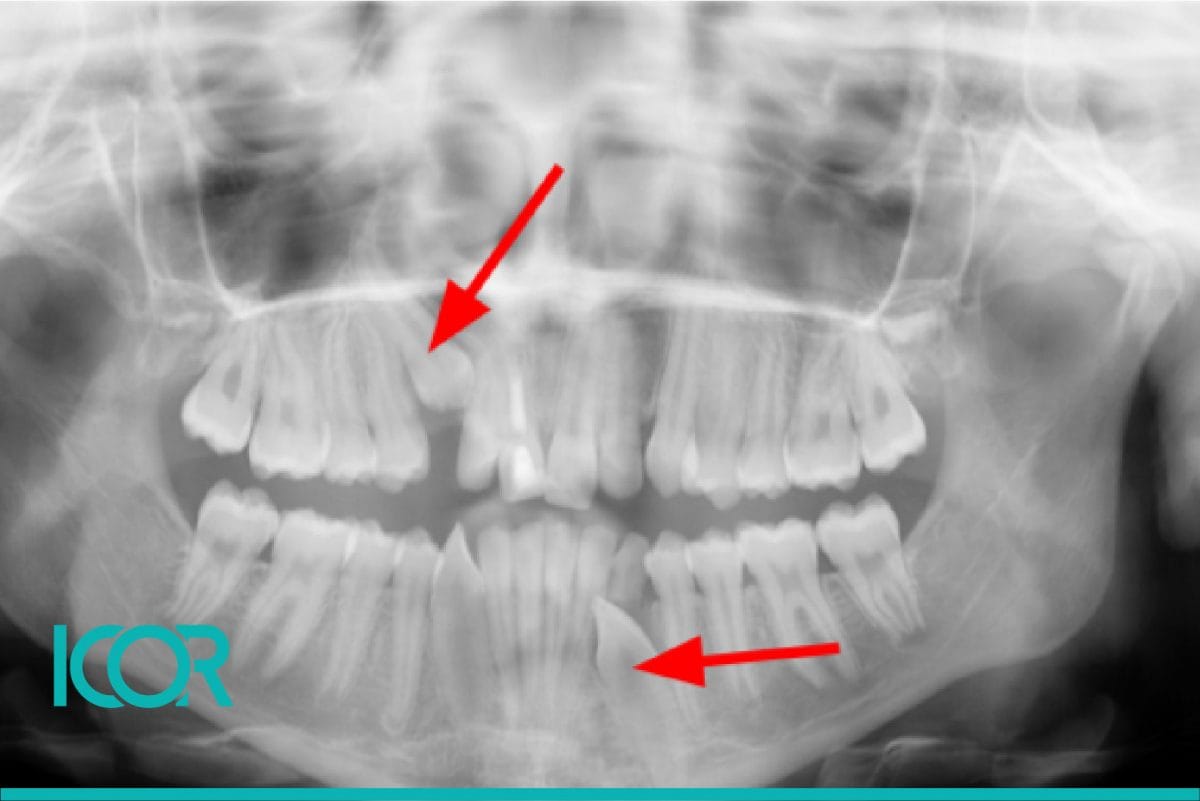

Joaquín llegó, con 4 años de edad, a consulta con la Dra. Milagros Tocornal para tratar su caso de mordida invertida.

El tratamiento de Joaquín se desarrolló en fases que fueron desde los 4 años hasta los 15 años.